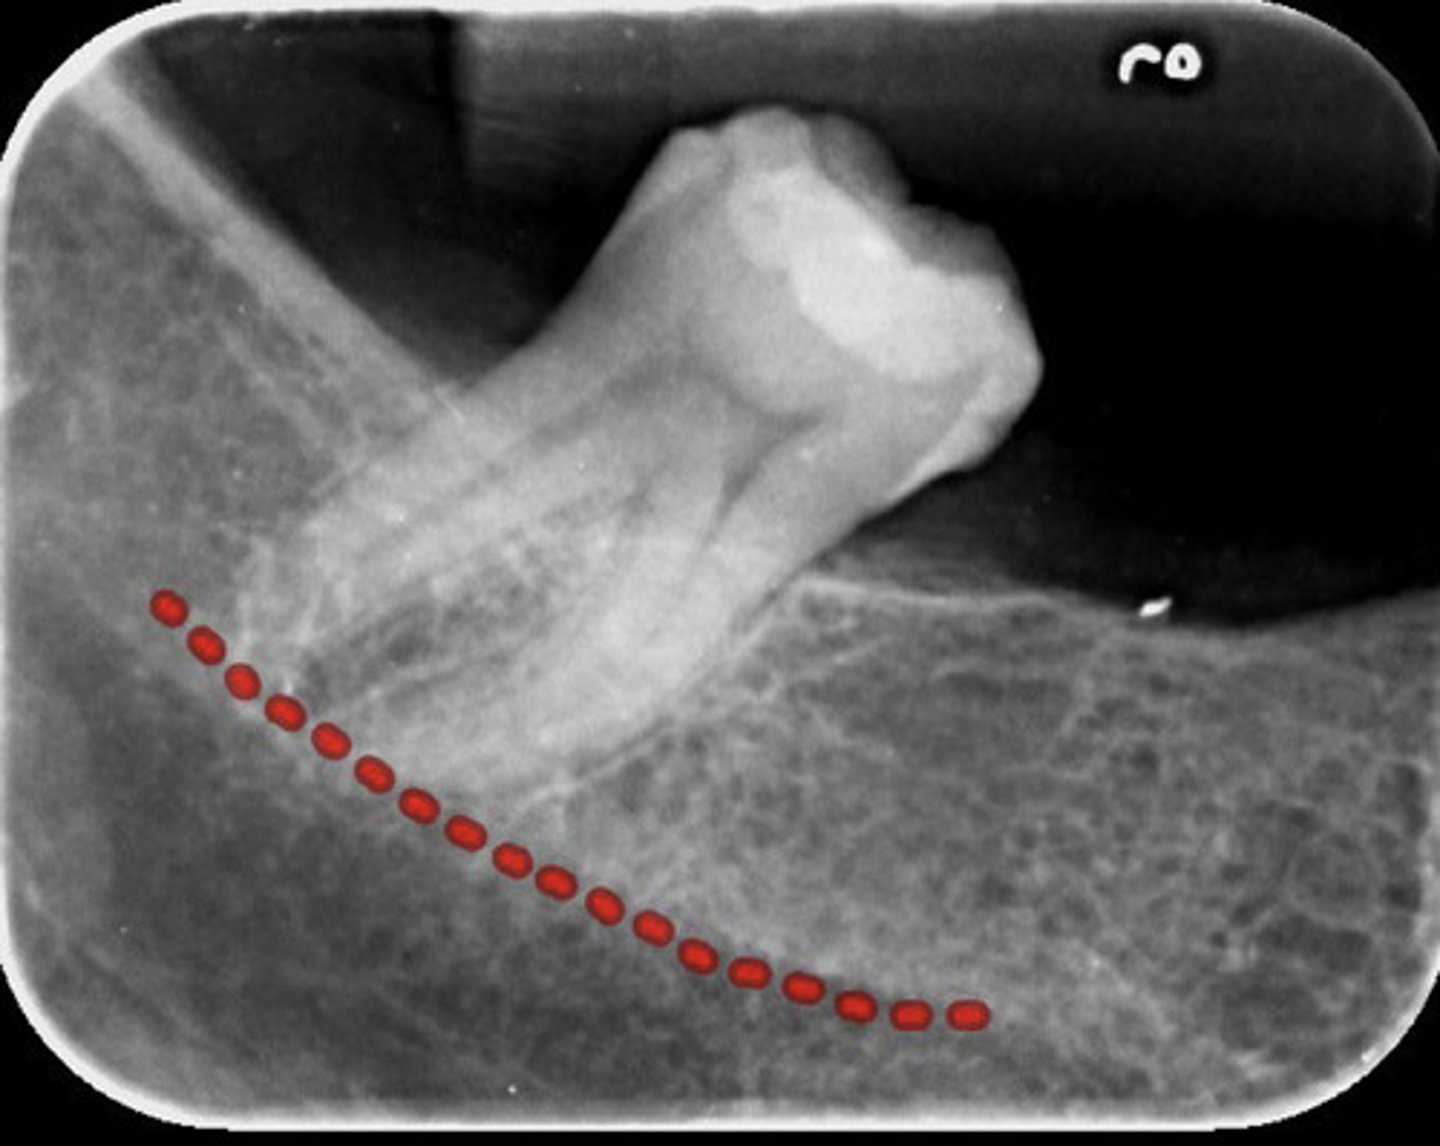

information on mylohyoid ridge

dense radiopaque band that extends downward and forward from the third molar region at the level of the apices of the posterior teeth

information on external oblique ridge

appears as a radiopaque band extending downward and forward from the anterior border of the ramus of the mandible

-starts behind last tooth and comes forward